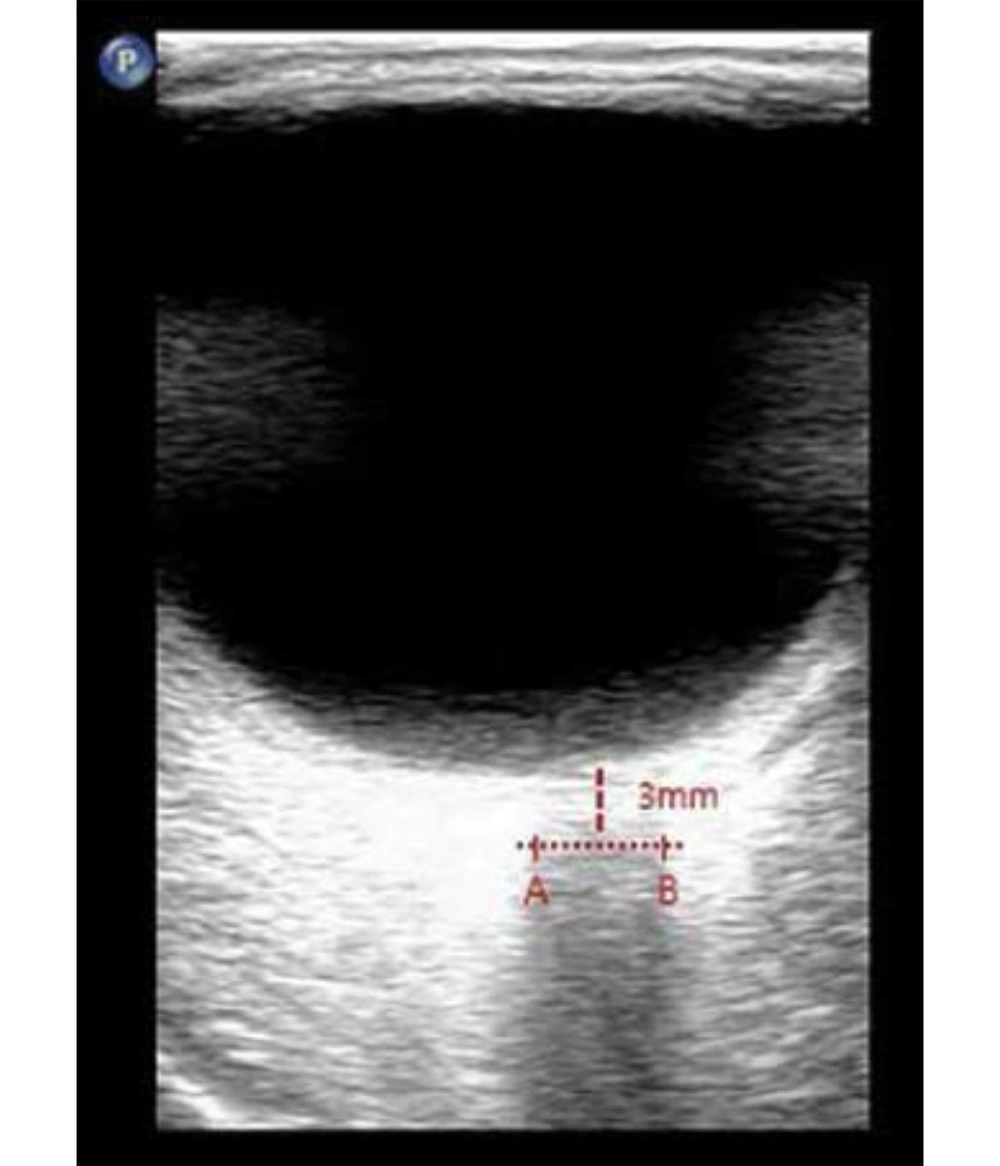

Direct invasive monitoring of ICP, the gold standard for assessment, is not feasible in routine interventional pain practice. Consequently, there is growing interest in the use of non-invasive surrogate markers to assess changes in ICP in real time. Among these, ultrasonographic measurement of the optic nerve sheath diameter (ONSD) has emerged as a validated and reliable approach (8-10). The optic nerve sheath, which is contiguous with the subarachnoid space, serves as a sensitive indicator; increases in ICP are rapidly transmitted to this compartment, resulting in measurable sheath expansion, particularly 3 mm behind the globe where distensibility is greatest (Figure 1).

- Bilateral ONSD was assessed in a transverse axial plane, 3 mm posterior to the optic disc, which is considered the most sensitive point for detecting changes in ICP (8-10).

Epidural injection of large fluid volumes can generate a transient rise in epidural and CSF pressures, attributable to the anatomical continuity between the epidural and subarachnoid spaces through the dural sheath. The subsequent cranial transmission of this pressure, as theorized in both physiological models and experimental observations (10-12), can result in a temporary elevation of ICP. The ONSD measurement — especially at 3 mm behind the globe, the area most physiologically responsive to ICP shifts — provides a sensitive and reproducible means of tracking these changes (11). Our findings, demonstrating an increase in ONSD after caudal injection, are consistent with this pathophysiological mechanism and concordant with changes reported in pediatric and non-FBSS adult cohorts following neuroaxial blockade or similarly voluminous epidural interventions (8, 9, 13).